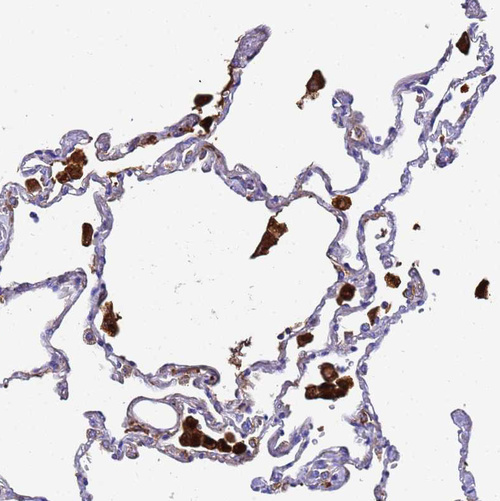

Immunohistochemistry analysis in human lung and skeletal muscle tissues using HPA041602 antibody. Corresponding FTL RNA-seq data are presented for the same tissues.